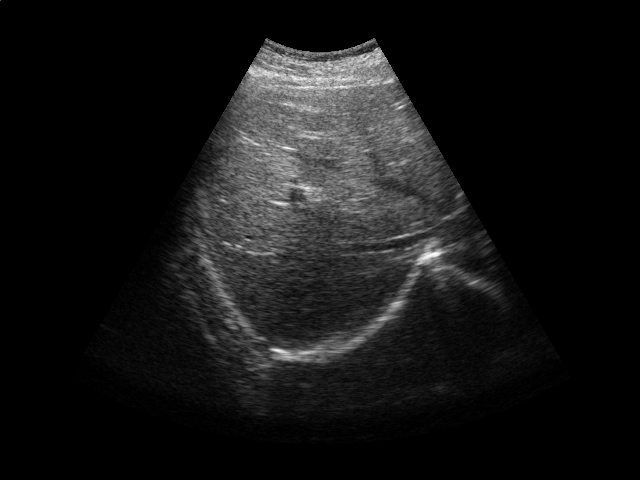

We conduct experiments on five 2D ultrasound image sequences of the human liver acquired during free breathing; example images are shown in Fig. 2. Each sequence contains 640480-pixel images and vary in length between 298 and 371 frames captured at 33 Hz. For a given image sequence, we use each image in the sequence as an input data point for learning a 1D manifold with Laplacian eigenmaps [4]; we use a 9-nearest-neighbor graph with an associated heat kernel of temperature . The 1D embedding learned using an entire sequence of images serves as a reference signal for evaluating our sparse out-of-sample extension versus kernel ridge regression as the baseline. In what follows, we compare the 1D embedding of our sparse out-of-sample extension to the reference signal by computing a correlation coefficient between them. We use kernel ridge regression as a baseline method. Here we train on the first 200 frames and test on the remaining frames. We then compare the results with those obtained by training on all frames, as would be done for retrospective gating.

We first examine the influence of parameters and on the resulting interpolator. Training on the first 200 images of one of the ultrasound image sequences, we compute the correlation coefficient with the reference signal and the number of support vectors versus the error tolerance (Fig. 2). As expected, smaller error tolerance requires more support vectors but also leads to a higher correlation coefficient with respect to the reference signal. Also, a higher kernel ridge regression regularization parameter leads to fewer support vectors. However, stronger regularization also leads to lower correlation coefficients. These results suggest a natural tradeoff between the accuracy and the computational cost of the projection operation.

In the next experiment, we use and . Training on the first 200 frames and testing on the rest of the frames, we report the correlation coefficients and the number of support vectors in Table 1. The number of support vectors for kernel ridge regression is 200 in this case. We then repeat the experiment, training on all the frames. In this case, the number of support vectors for kernel ridge regression is the length of the sequence. We achieve a high correlation for all sequences, with a comparable performance between our sparse interpolator and kernel ridge regression. Comparing the number of support vectors when training on the first 200 frames vs. training on all the frames, we note that the number of support vectors stays roughly the same for a given image sequence. This again suggests that the number of support vectors depends on the low-dimensional embedding’s complexity and not the training set size.